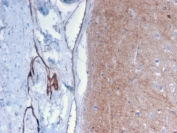

IHC staining of FFPE human brain with Drebrin 1 antibody (clone DBN1/2879). HIER: boil tissue sections in pH 9 10mM Tris with 1mM EDTA for 10-20 min followed by cooling at RT for 20 min.